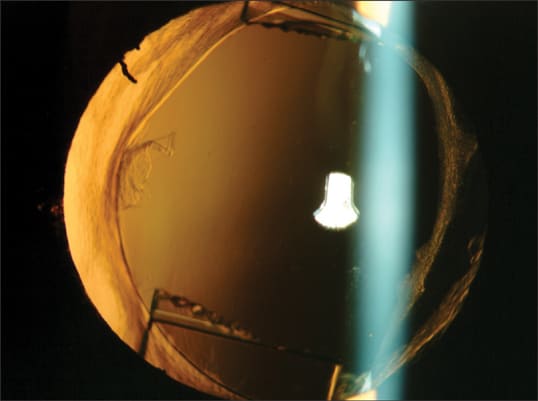

Figure 1. Image from a dissatisfied patient who had a Crystalens accommodating implant and then a YAG laser posterior capsulotomy (note pits) for early PCO.

Figure 2. With an open capsule after YAG laser, the same patient remained dissatisfied and underwent an IOL exchange, cutting the hinges of the Crystalens and resting a Monofocal Aspheric IOL on the residual IOL fragment within the capsular bag. Due to weakened zonular support, the entire Crystalens implant could not be explanted, necessitating cutting out the optic at the hinges.